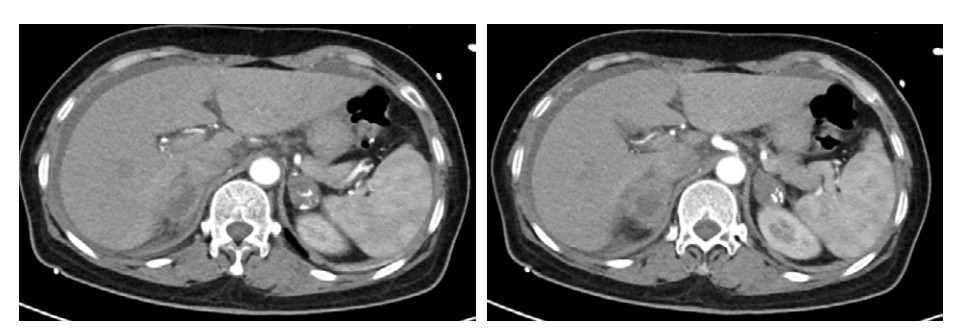

医嘱给予哌拉西林他唑巴坦抗感染,补液扩容、补充血钠,去甲肾上腺素2.7 μg/(kg·min)持续泵入,期间血压波动在78~100/51~69 mmHg之间。患者血压对去甲肾上腺素呈明显依赖,在补充1 000 mL胶体及1 700 mL晶体后,去甲肾上腺素一旦减量血压即降低到上述下界值。经补液后患者尿量维持250 mL/h。床旁超声可见下降静脉宽度由入院时的1.0 cm增加至1.9 cm。由于CT提示肾上腺占位,遂请内分泌科会诊, 考虑肾上腺占位伴肾上腺危象可能,遂完善腹部增强CT可见双侧肾上腺增大,不规则,伴少量钙化(图 2)。03-03晨8:00测血皮质醇14.96 ng/mL (52.7~224.5 ng/mL)、促肾上腺皮质激素1 096 ng/mL (≤ 46 ng/mL),加用氢化可的松200 mg快速静滴,随后200 mg静脉泵入维持24 h,2024-03-03日下午患者神志清楚,精神状态改善,恢复自主进食,血压逐渐上升并维持在130~140/60~85 mmHg,血钠130 mmol/L。03-04日,患者神志清楚,GCS评分15分,去甲肾上腺素减停,血压波动在125~130/58~86 mmHg左右,继续予以氢化可的松200 mg静脉泵入维持,当日下午转入内分泌病房继续治疗。住院期间氢化可的松用量情况见(图 6),03-09日停用氢化可的松后改为醋酸泼尼松片口服,日剂量为8:00 5 mg,16:00 2.5 mg。期间查T-spot阳性,抗核抗体谱、自身免疫性抗体、病毒学均阴性。出院诊断: 原发性肾上腺皮质功能不全,肾上腺危象。症状好转后于2024-03-13日出院,出院继续维持醋酸泼尼松片8:00 5 mg,口服,16:00 2.5 mg,口服用药方案。随访至今,患者一般情况良好,可从事简单体力劳动。

| 图 2 腹部增强CT双侧肾上腺强化不均伴有点状钙化灶 |